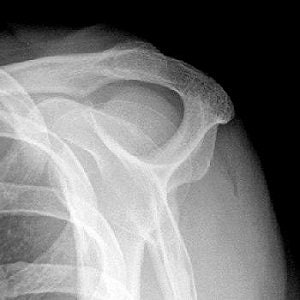

![]() |

| Mathematic determination of acromial shape. Line connecting most caudal points of acromial undersurface is drawn on parasagittal T2-weighted MR image, and with help of two orthogonal lines, acromion is divided into three segments of equal length. |